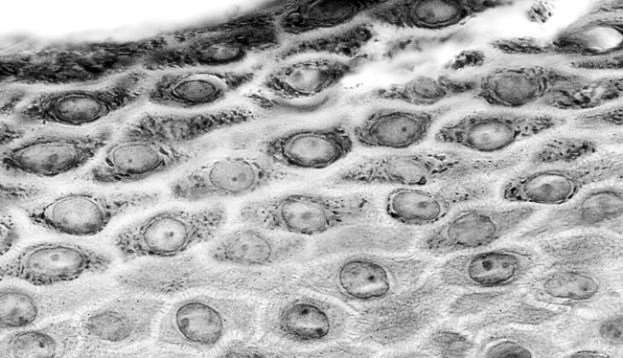

При повреждении кожного покрова тяжесть и последствия травмы зависят от количества пораженных слоев – чем глубже поражение, тем серьезнее травма. К счастью, кожа является одной из самых быстро восстанавливающихся частей тела. Подробнее о целительных способностях кожи см. параграфы «Реакция на занозу» и «Обитель тромбоцитов» на стр. 157–161. Эпидермис Верить в то, что эпидермис – это не более чем верхний слой кожи, простительно. Но если копнуть чуть глубже, выяснится, что сам эпидермис состоит из нескольких слоев, число которых может доходить до пяти. Самый нижний слой эпидермиса – это базальный слой. Он располагается чуть выше дермы и образуется одним слоем «живых» эпителиальных клеток (см. параграф «Квартет тканей» на стр. 43). Такие клетки называются кератиноцитами. Остальные слои эпидермиса состоят из клеток, которые в буквальном смысле доживают последние дни. И действительно: эпидермис – это место, где мертвые покоятся над живыми. ![]() На этом микроснимке показаны клетки эпидермиса. Клетки всех слоев над самым глубоким, или базальным, слоем называются кератиноцитами. Постепенно они отмирают, сплющиваются и затвердевают, а под давлением новых клеток выталкиваются ближе к поверхности. Зародышевый слой – зачастую так называют базальные кератиноциты. Они постоянно делятся и создают новые клетки, которые затем выталкиваются в поверхностный слой. В процессе этого движения кератиноциты вырабатывают белок – кератин, который придает эпидермису прочность и водостойкость. По мере продвижения на поверхность кератиноциты сплющиваются, теряют ядро, затвердевают и умирают, лишая верхний слой живых клеток. Этот верхний, или роговой, слой отпадает в результате ежедневной активности человека. Крайне важно, чтобы клетки в базальном слое обновлялись с той же скоростью, с которой они отмирают в роговом слое. Дисбаланс может привести к развитию псориаза. При такой патологии клетки заменяются слишком быстро (каждые 3–7 дней) и скапливаются в утолщенных чешуеобразных пятнах. Создан защищать Толщина кожи по всему телу неоднородна. Она зависит от количества слоев эпидермиса и интенсивности воздействия, которому подвергается кожа. Самый тонкий участок кожи – веки, а самый толстый – ладони и ступки. В них, помимо стандартных четырех слоев эпидермиса, присутствует еще и пятый. Также в эпидермисе содержатся иммунные клетки – клетки Лангерганса, которые очищают кожу от инвазивных микроорганизмов. ![]() Кератиноциты в нижних слоях эпидермиса склеиваются между собой в определенных участках – десмосомах, что повышает механическую прочность кожи. ![]() Эта модель показывает молекулярную структуру белка кератина, который присутствует в эпидермисе, волосах и ногтях. Базальная мембрана Эпидермис крепится к следующему слою – дерме – с помощью межклеточного вещества, которое называют базальной мембраной. Эта мембрана выполняет адгезивную функцию, а также защищает нижние структуры кожи от потенциально опасных объектов, включая наши собственные клетки, которые могут мутировать и превращаться в злокачественные. ![]() Меланин защищает ДНК наших клеток от вредного ультрафиолетового излучения. Он поглощает ультрафиолетовые лучи, отводя их от ДНК. Нарушение этого процесса вызывает мутацию, способную привести к развитию рака. Цвет кожи Люди всех цветов кожи вырабатывают одинаковое количество меланоцитов. Темный оттенок кожи определяется степенью активности меланоцитов и количеством дендритов, которые могут «дотягиваться» до других клеток. У темнокожих людей более крупные меланоциты. Такие клетки вырабатывают больше меланина, а большее количество дендритов в клетках охватывает большую поверхность кожи. Как бы странно это ни звучало, но у альбиносов тоже есть меланоциты, однако их способность вырабатывать и распространять меланин ограничена генетической мутацией. Все это приводит к тому, что кератиноциты лишаются пигмента. Родинки, или невусы, образуются при скоплении групп меланоцитов. Веснушки появляются, когда под действием ультрафиолета гиперактивные меланоциты начинают вырабатывать много меланосом. И группы кератиноцитов в огромном количестве поглощают эти меланосомы. ![]() Чаще всего веснушки встречаются у бледнокожих и рыжеволосых людей, поскольку такие люди являются носителями варианта гена MC1R. Меланоциты Одной из популяций клеток, которая чаще всего превращается в злокачественную, являются особые клетки – меланоциты. Эти клетки располагаются вдоль базального слоя и вырабатывают темный пигмент меланин. Именно он придает окрас нашей коже, волосам и радужной оболочке глаз. Это возможно благодаря дендритам – пальцевидным отросткам цитоплазмы меланина. Дендриты встречаются не только у меланоцитов, они широко распространены и в нервных клетках. Меланоциты и клетки нервной системы очень похожи, ведь когда-то, когда мы еще были развивающимися эмбрионами, группа клеток, которой суждено было стать меланоцитами, отделилась от области, из которой в дальнейшем сформировался спинной мозг. Меланоциты, как альтруистичные осьминоги, упаковывают меланин в гранулы (меланосомы) и распределяют их по соседним кератиноцитам для дальнейшего всасывания. Оказавшись внутри, меланосомы распадаются, а клетки наполняются меланином. Это «клеточное подношение» повторяется по всей поверхности кожи, делая ее способной разрушать ультрафиолетовое излучение. Дерма Эпидермис аваскулярен, то есть в нем отсутствуют кровеносные сосуды. Именно поэтому поверхностные порезы кожи не кровоточат и болят не так сильно. Однако если рана рассекает эпидермис насквозь, то обнажается белоснежный слой плоти, и начинается кровотечение. Если травма доходит до дермы с ее внутренними системами восстановления и сетями кровеносных и лимфатических сосудов, то после заживления остается шрам. Этот толстый слой соединительной ткани отвечает за питание эпидермиса. Скрученные белковые волокна коллагена и эластина помогают дерме создавать прочный и эластичный каркас, который позволяет нашей коже растягиваться и сжиматься. Между этими волокнами располагается целая популяция различных структур. ![]() |